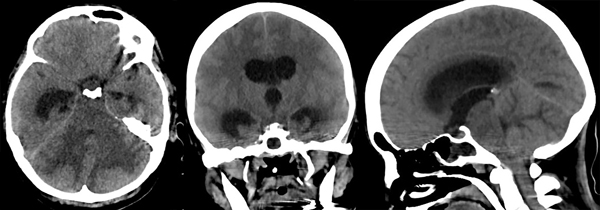

Se trata de una mujer de 47 años, portadora de angeítis de Wegener con compromiso pulmonar severo y otras comorbilidades, que requirió asistencia ventilatoria mecánica (AVM) por insuficiencia ventilatoria y posteriormente traqueostomía. Luego de varios días en AVM desarrolló en el transcurso de pocas horas estupor y deterioro de la respuesta motriz; la TC de encéfalo sin contraste mostró hidrocefalia aguda obstructiva por lesión de fosa posterior (Figura 6).

Figura 6: Tomografía computada del encéfalo donde se aprecia edema cerebeloso con compresión del tronco cerebral e hidrocefalia supratentorial aguda.